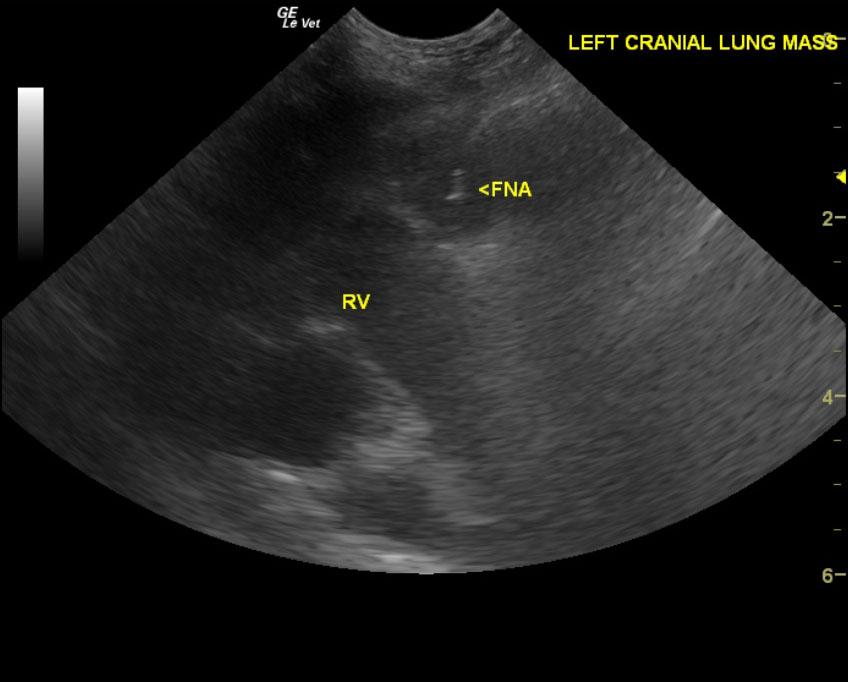

A 12-year-old FS Kerry Blue Terrier dog was presented for evaluation of poor appetite and not being himself. He also had a history of periodic lethargy.